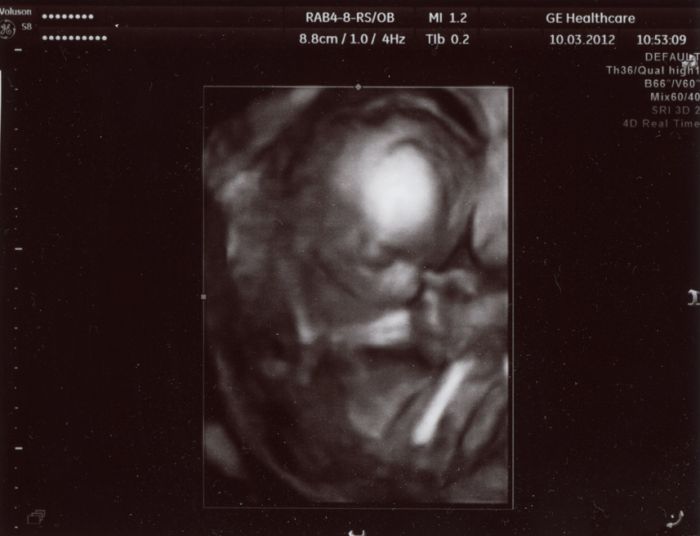

Ahoj holky :-) Až teď píšu, protože jsem po UZ hned jeli pryč na víkend. Takže hlásím, že je vše v pořádku. Miminko má od hlavičky po zadeček 15cm, mrskalo se tam a pořád se šťouralo v oušku nebo v očích. Dr. si nejdřív myslel, že je to kluk, ale pak znejistěl, neboť tam nic neviděl, nebo spíš to nebylo úplně jasně vidět. Každopádně jasnej pindík tam sice vidět nebyl, ale nechtěl nám s jistotou potrvzovat holčičku, co kdyby tam dole ještě něco narostlo??!! ;-) Takže opět nevím nic, ale my se přikláníme k tomu, že to bude holčička ;-)

Tady je pár foteček. Video dostanu za 2 týdny až tam půjdu na kontrolu. Ten jeho přístroj mu to nedovede hned zpracovat, tak nám to video nemohl hned dát.

Tedy Blanko, to jsou fakt nááádherné fotečky!

Fakt krásně vyfocené....Tak to moc gratuluji!

Člověče,nevím proč, ale také mi to miminko přijde jako holčička